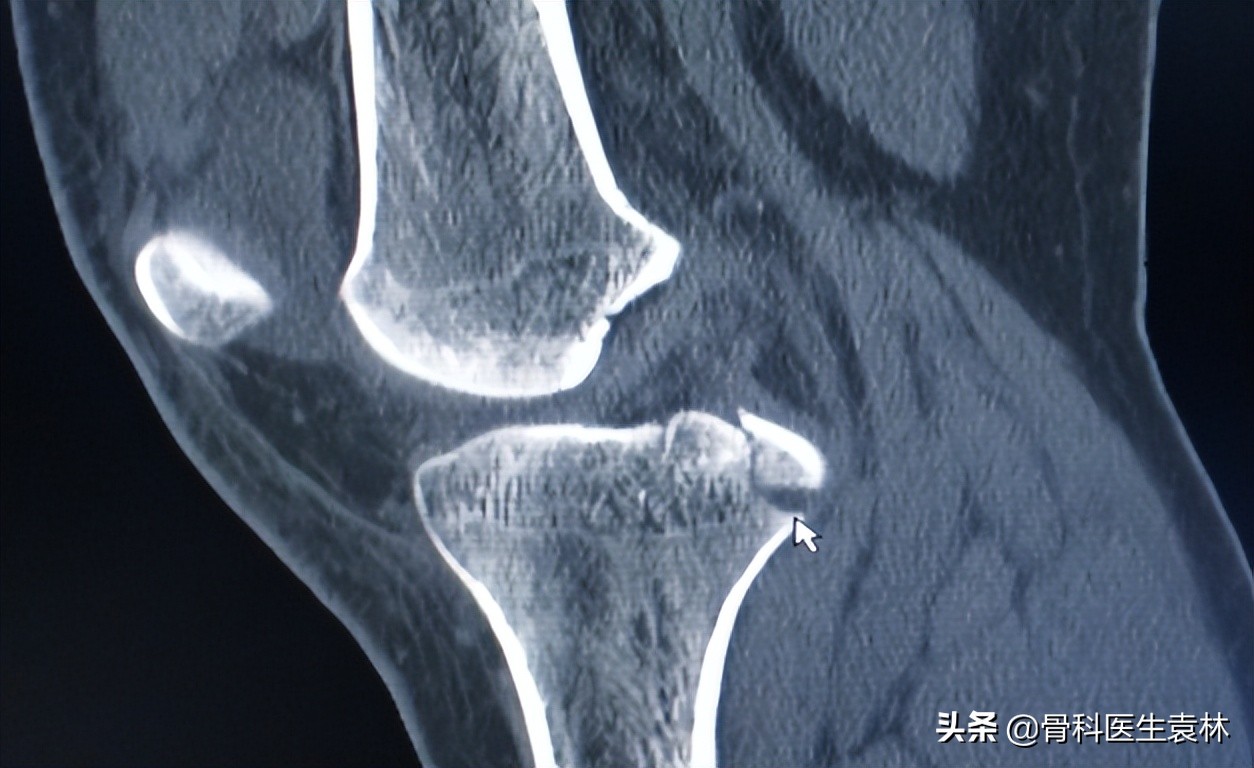

在人年轻的时候,软骨表面很光滑,软骨间的滑液还很充足,膝关节可以活动自如。随着年纪的增长,软骨细胞变性、退变,软骨下的骨头、韧带、关节囊、滑膜、肌肉都在老化,人体关节软骨不可避免地发生退化和磨损。

膝关节在人体中属负重最大和运动最多的关节,因而也是人体中退化最早、损伤最多的关节。尤其是绝经后的女性,由于其体内激素水平下降,会引起膝关节软骨退化、萎缩。

不当地使用膝关节、外伤也会加速关节软骨的磨损。一些爬或蹲的家务活、爬山等运动,都会增加关节负担,广场舞中一些增加膝关节负荷的动作,也最好避免。